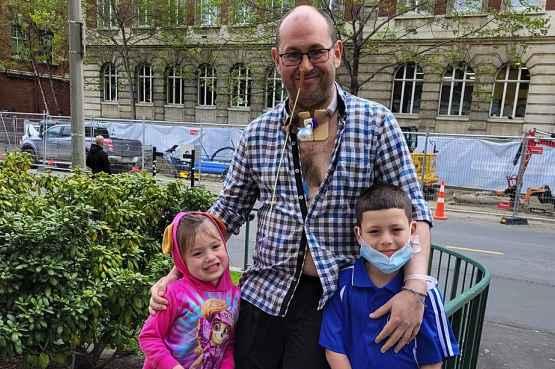

Appeal fordad with incurable cancer

AWolverhampton family haslaunchedanappealtoraise £25,000forurgenttreatmentafter afather-of-twowastoldhehasjust monthstolive

AndyDalton,41,fromFinch field,butnowlivinginNewZea land,wasdiagnosedwitharare incurablecancerafew weeks agoafterinitiallygoingtovisita doctorbecauseofashortnessof breath

Nowhisfamilyandfriendsare organisingafundraiserinthecity tohelpsupporthischildrenand payfortreatmentthatmaypro longhislife

AndithasthebackingofSlade guitaristDaveHill whowill be makinganappearanceattheevent thisweekend

Andy wasdiagnosedwitha rare andaggressiveanaplastic thyroidcancerafteritwasfound tobeblockinghisairwayandit wasunabletoberemovedduring surgery.Thefathernowhasatra cheostomymeaninghecannottalk andistoopoorlytotravel.

Andy’s family saythe treat ment he requires to prolonghis lifeisnotfundedonthehealthcare systeminNewZealandandwould needtobeprivatelyfunded.They

hopetoraise$50,000,whichisthe equivalentofaround£25,000.The fundaywilltakeplaceonSunday attheVictoryHallinGreyhound LaneinLowerPennbetween2and 5pm.Allarewelcome.Meanwhile, theDaltonfamilycontinuetheir onlinefundraisingcampaign.

Theyalreadyhavemorethan 50raffleprizesincludingaweek endaway,three£100Smythstoys vouchers andseveral restaurant andbeautyvouchers–alldonated

bycompaniesacrossWolverhamp ton.DaveHillwillmaketheGrand Raffledrawandannouncethewin ners.

Currently,Andyisundergoing radiationtreatmentandstartinga newtreatmentplan.

Fulldetailsoftheeventcanbe foundonFacebook:facebook.com/ events/1278285619694967

Donate to thefundraiserat givealittle.co.nz/cause/doing-itfor-dalton

Andy Dalton withhis childrenEmmy, four, andZavier, eight